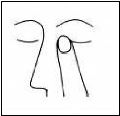

4. LATROST-T kullanımından soma, parmağınız ile gözünüzün kenarmdan burnunuza doğru aşağıdaki şekilde gibi 2 dakika bastırınız. Bu latanoprost ve timololün

vücudunuzun diğer bölümlerine geçişini engellemeye yardımcı olacaktır.